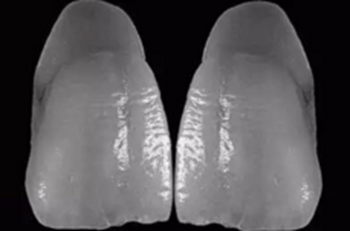

13、可以清晰的辨別出修整的頸線和肩臺是否有誤差

14、在工作模完全就位的義齒

15、在檢測模上可以看出左上1頸線有誤差